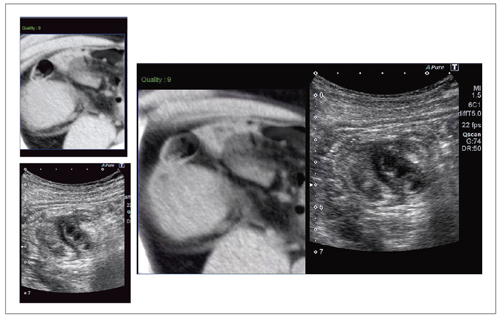

CT画像をナビゲーションとして観察できる“Smart Fusion”

Smart Fusion は,CTなど他のモダリティのボリュームデータと超音波画像を連動表示するアプリケーションである。Aplio 500本体に取り付けたアームから磁場を発生させ,プローブで受信することで位置を測定し,位置合わせは座標軸と基準(目印)の2ステップのみと,“Smart”に設定できるのが特長である。Smart Fusionでは,超音波画像とCT画像を互いに補い合って確認ができるため,診断での有用性はもちろん,解剖やCT読影のトレーニングにもなり,教育にも有用である。

図9は,腹部膨満感,下腹部痛で来院した70歳代,男性の回盲部CT画像とのSmart Fusionである。CTでは腫瘤の存在や炎症像の確認はできるが,内部の構造は不明瞭である。超音波では,腫瘍内部の重積様変化が明瞭にとらえられた。高度に肥厚した腸管壁のエコーレベルは,均一な低エコーを呈していた。周囲には,炎症を反映した強いisolation signが見られた。また,一塊となった腫瘤は大きく,CT画像が回腸末端から連続する腫瘤像を的確にとらえ,エコー像をナビゲーションし情報を得た。Smart Fusionの活用により小腸リンパ腫(回腸末端部)が回盲部から盲腸へ隆起し,回腸・結腸型の腸重積様に一体化した腫瘤を形成した病態と診断できた。緊急手術が施行され,術前診断と一致した手術所見であった。

図9 70歳代,男性,悪性リンパ腫の小腸病変に施行したSmart Fusion画像